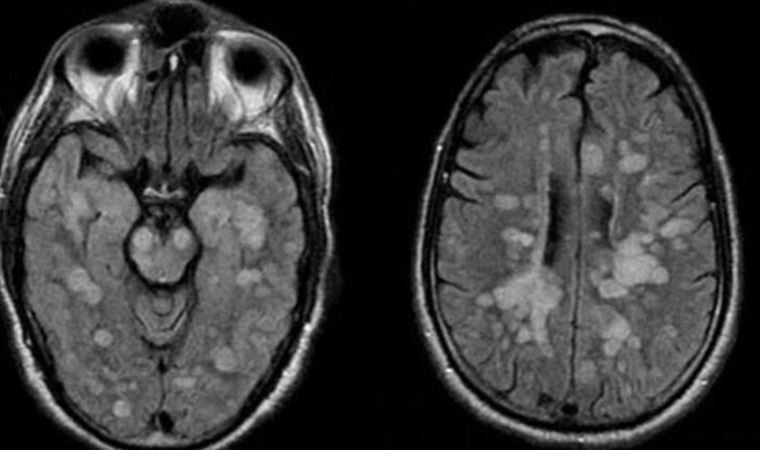

Talihsiz çocuğa vücudun bağışıklık sistemi kendisine saldırarak omurilik ve beynin şişmesine neden olan nadir bir akut yayılmış Ensefalit (ADEM) teşhisi koyuldu.

Braun’un Akut dissemine ensefalomyelit (ADEM) santral sinir sisteminin immun aracılıklı bir bozukluğuna yakalandığı bildirildi.